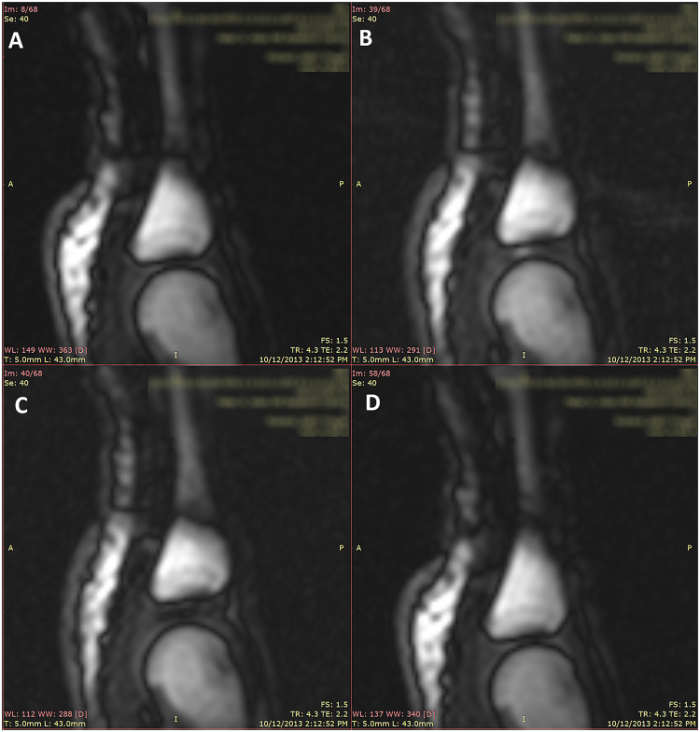

На рис. 4 представлены 4 кадра, снятые на пястно-фаланговом суставе 4 пальца правой руки. Рис. 4А — фаза восстановления, рис. 4B — период до хруста, рис. 4C — период после хруста, рис. 4D — кадр после расслабления пальца.

Kawchuk G. и его коллеги — первые, которые решили использовать МРТ-съемку с целью показать, как именно формируется характерный звук хруста в суставе и при каких обстоятельствах. Ученые доказали, что механизм возникновения суставного хруста ближе к кавитации, нежели схлопыванию пузырька воздуха. И тем самым подтвердили точку зрения Roston B. и Haines W., которая подразумевала, что характерный звук хруста появляется в момент формирования пузырька, а не схлопывания.